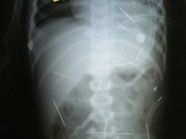

Die Röntgenbilder mit Nadeln

An den Ritualen seien wahrscheinlich außer dem Vater noch weitere Menschen beteiligt, sagte Pacheco. Wegen der noch laufenden Ermittlungen könne er aber keine Einzelheiten nennen. Die Eltern des Kindes hatten demnach zunächst jede Verwicklung in die Misshandlung des Kleinkindes abgestritten. Allerdings wurde ihnen das Sorgerecht bereits aberkannt und den Großeltern übertragen. Im August hatten Ärzte bei einer Röntgenuntersuchung sieben Nadeln im Magen des Kindes entdeckt, von denen bisher zwei herausoperiert wurden.